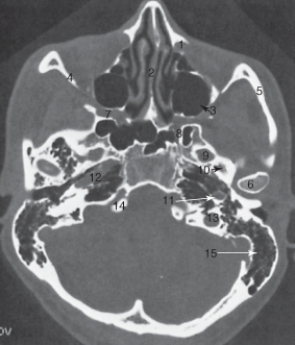

The zygoma is labeled:

A)6.

B)7.

C)8.

D)9.

22

The structure labeled 5 is the:

A) lateral orbital wall.

B) mandibular condyle.

C) temporal bone.

D) zygomatic arch.

23

The nasal septum is labeled:

A)1.

B)2

C)3.

D)4.

24

The structure labeled as 1 is the:

A) internal carotid artery.

B) masseter muscle.

C) odontoid process.

D) spinal cord.

26

The mastoid air cells are labeled:

A)3.

B)11.

C)12.

D)15.

30

The sphenoid sinus is labeled:

B)2.

D) 5.

32

The structure labeled 3 is the:

A) cribriform plate.

B) inferior turbinate.

C) maxillary sinus.

D) middle turbinate.

34

The lateral orbital wall is labeled:

35

The ethmoid sinuses are labeled:

A)2.

B)3.

C)4.

D)5.

40

The structure labeled 6 is the:

A) ascending carotid canal.

B) lateral orbital wall.

C) nasal septum.

D) mandibular condyle.